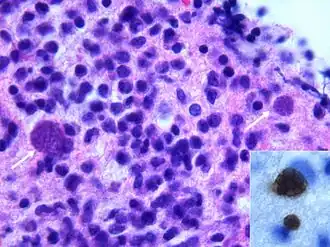

- Il se reproduit rapidement par un processus de multiplication asexuée (endodyogénie) chez l’hôte intermédiaire, toujours dans des macrophages. Puis il en sort en perforant la paroi au moyen d’une protéine qu’il produit (perforine). Des parasites génétiquement modifiés pour ne pas produire cette protéine ne peuvent sortir du macrophage qui gonfle en formant une boule[17]. Visuellement, l’enveloppe du parasite a la forme d’une goutte d’eau un peu arquée (toxon en grec signifie « arc »), d’environ 6 à 8 μm de longueur et de 3 à 4 μm de largeur. Le pôle postérieur arrondi contient le noyau tandis que le pôle antérieur plus aigu possède des ultrastructures adaptées à la pénétration cellulaire (complexe apical).

- Cette forme est plus résistante que la précédente (forme de résistance et de dissémination), entourée par une membrane épaisse, de forme sphérique ou ovoïde, elle mesure de 50 à 200 µm. Elle contient en plusieurs milliers d’exemplaires une forme végétative particulière le bradyzoïte ou cystozoïte (3 à 4 microns), un kyste de 100 µm en contient 2 000 à 3 000. Les bradyzoïtes résultent d’une série de multiplications asexuées, colonisant l’intérieur d’une cellule hôte. Leur multiplication est assez lente, et ne peut se faire que dans une cellule nerveuse ou musculaire de l’hôte intermédiaire. Dans les tissus, les kystes restent longtemps vivants, produisant des antigènes qui entretiennent l’immunité. Les kystes peuvent survivre plusieurs jours à température ambiante et plusieurs mois à 4 °C. Ils sont détruits par la chaleur (un quart d’heure à 56 °C) ou la congélation (24 heures à −20 °C)[18].

- L’oocyste coccidien est très résistant, même à l’eau de Javel (forme de résistance et de dissémination), c’est la forme que l’on retrouve dans le milieu extérieur (sol, plantes…) où il effectue sa maturation en quelques jours (de un à cinq) à température ambiante et en présence d’oxygène. Sa résistance lui permet de rester vivant pendant plusieurs mois dans le sol, mais il est détruit par la chaleur lors de la cuisson, la dessiccation ou la congélation (−30 °C). Il est le résultat de la reproduction sexuée du parasite chez le chat. C’est un ovoïde de 15 µm par 10 µm regroupant 2 sporocystes de 6 à 8 µm de diamètre, contenant 4 sporozoïtes chacun (un sporozoïte ressemble à un tachyzoïte).